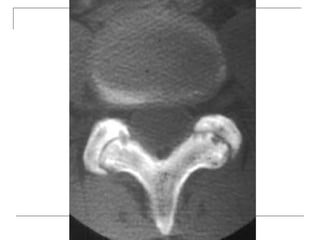

CT Scan

       better visualization of bone pathology (eg.

cortical destruction)

     fracture

     tumor

CT Scan  better visualization of bone pathology (eg. cortical destruction)  fracture  tumor